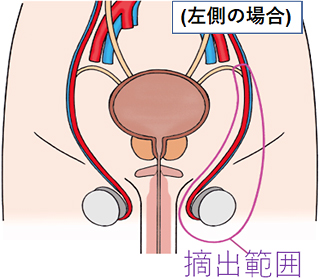

1.高位精巣摘除術

精巣腫瘍を強く疑う場合、基本的に全員に実施される手術です。精巣は血管と精子の通る精管が束になった精索という管でお腹の中とつながっています。精巣がんは、この精索を通り転移することが多く、精巣を摘出する際には陰嚢内の精巣だけでなく、精巣につながっている精索の上の方まで取り除きます。

そのため、摘出する側の下腹部の鼠径部を切って手術を行います。この手術方式を高位精巣摘除術といいます。

高位精巣摘除術の範囲